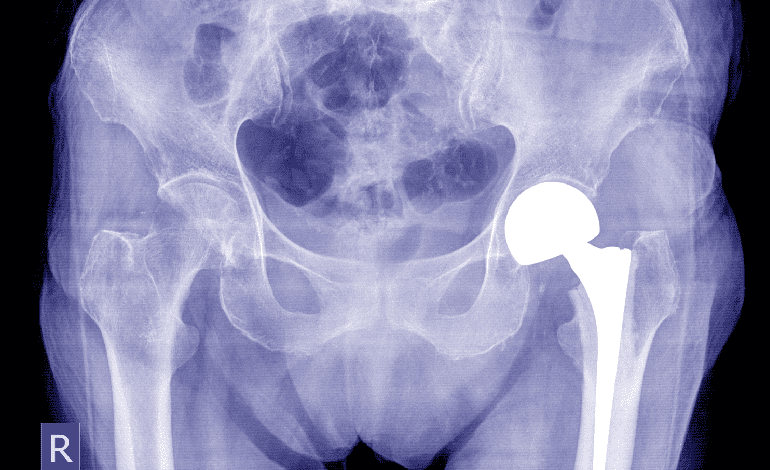

¿Buscas un médico especialista en Traumatología y ortopedia en Zapopan?